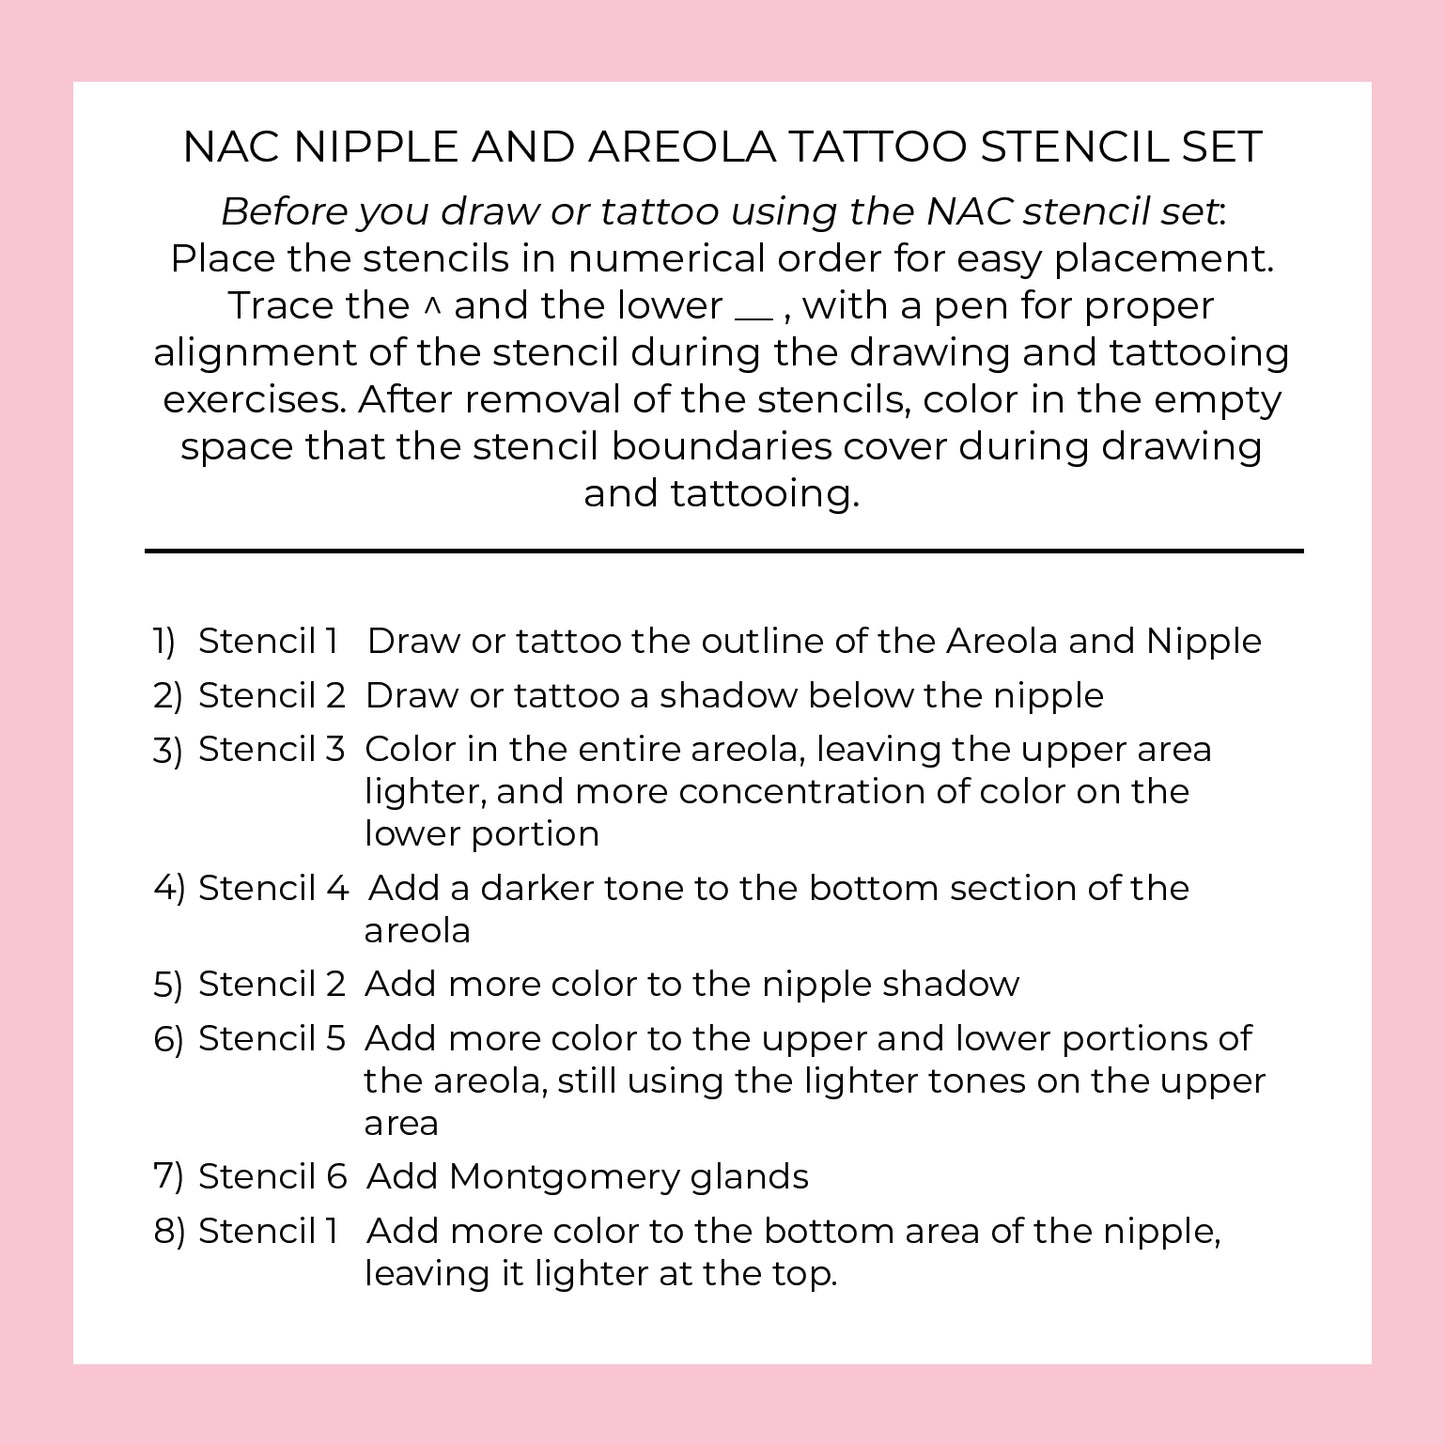

Creating a realistic, 3-D nipple/areola tattoo can be challenging — especially for new technicians learning the process. This 3-D Areola Tattoo Stencil Set is designed to simplify and guide you through each stage of areola restoration. With 6 professional-grade stencils and an 8-step workflow, you’ll have a clear visual roadmap while leaving space for your artistic interpretation and shading techniques to shine.

Made from 10mil polycarbonate film, these stencils are impact-resistant, clear, and durable — safe for practice pad work and even direct use during live procedures. They are steam autoclavable, alcohol-safe, and compatible with Sani-Cloth wipes, making them easy to clean and reuse safely. Ideal for PMU artists, medical tattooists, and professionals offering breast reconstruction finishing, scar camouflage, or restorative areola tattooing.

Whether you’re practicing at home or working in a medical aesthetics setting, this stencil set helps reduce overwhelm, speed up learning, and increase confidence for both students and professionals.